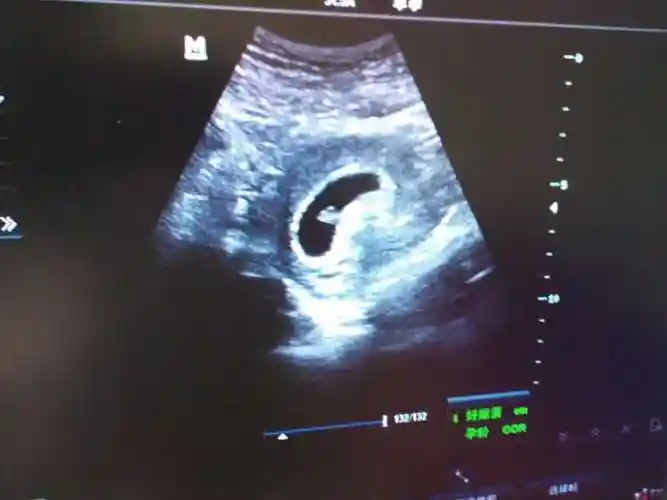

怀女宝孕囊,长是宽的两倍,准吗?

孕囊的形状一般是呈椭圆形或者是月亮型.